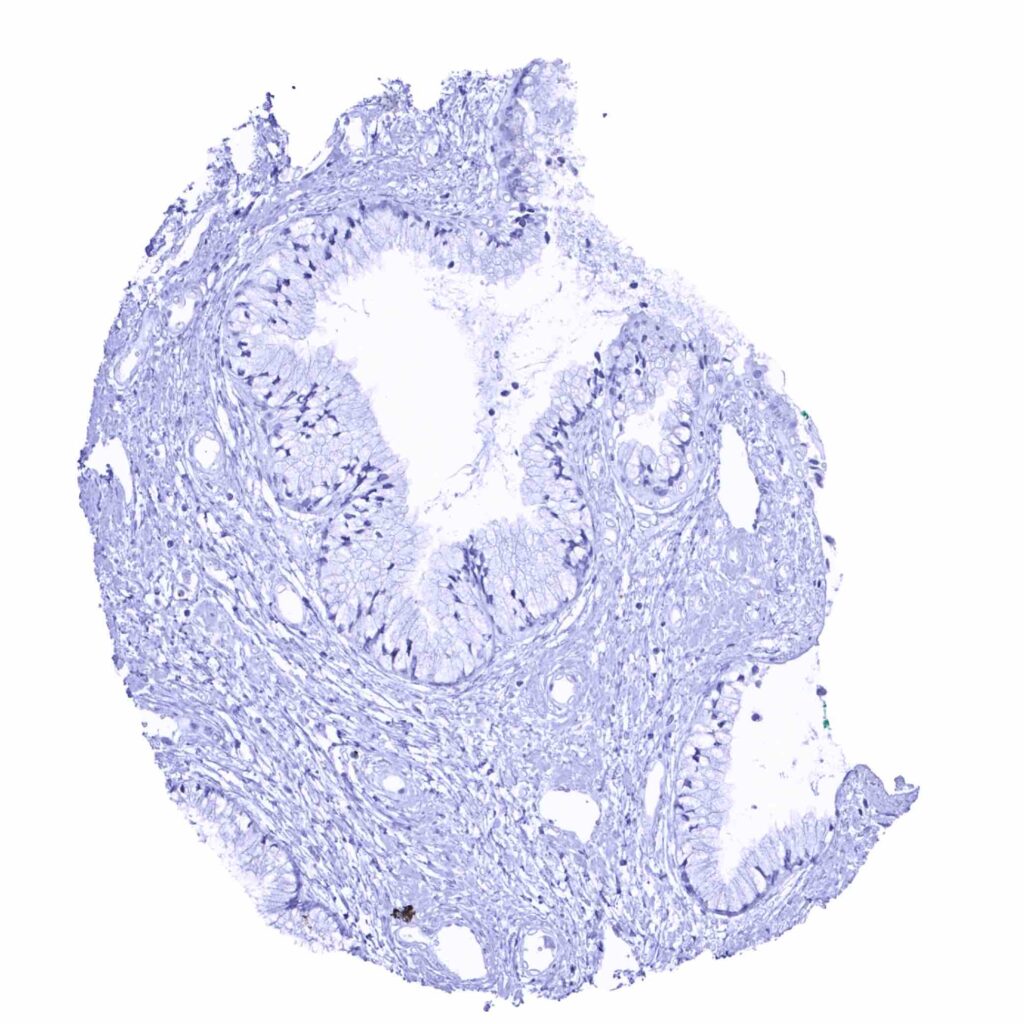

Appendix, mucosa – Prostein staining is lacking